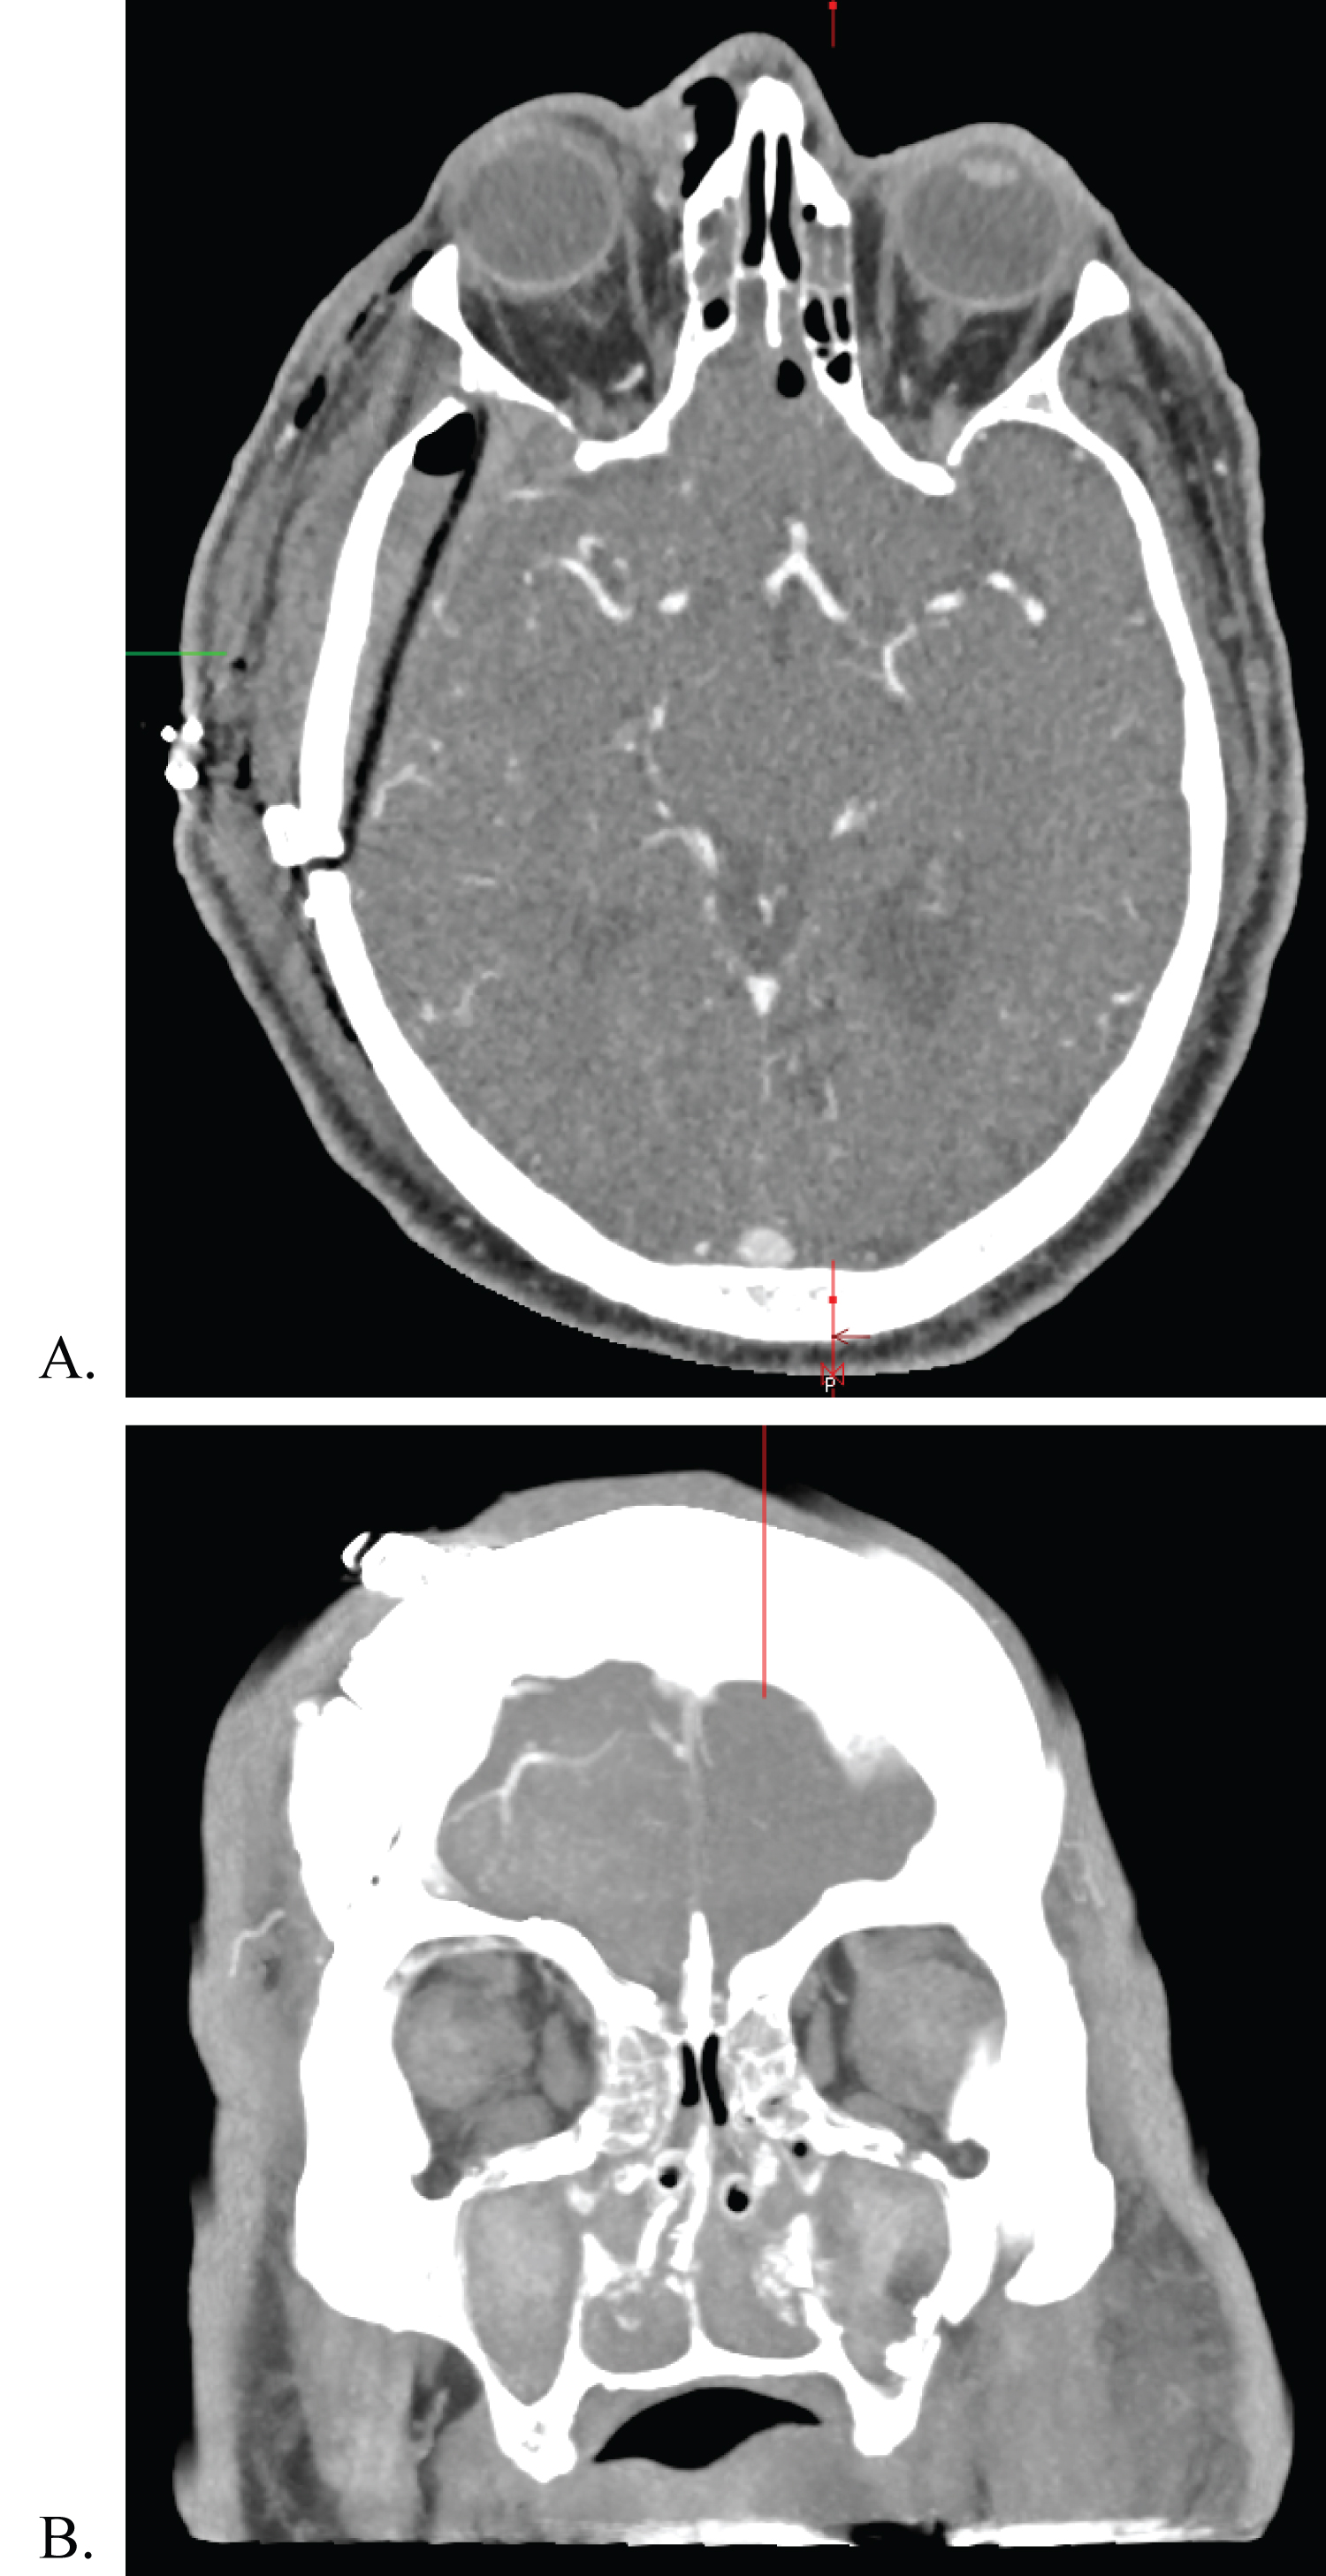

Post-operatively, he was admitted to the neurosurgical intensive care unit and started on intravenous ampicillin/sulbactam. He had persistent right sided ophthalmoplegia with ptosis, and complete loss of light perception in the right eye. Left sided extraocular movements, pupillary function, and visual acuity remained intact. There was reduced sensation in the ophthalmic distribution of the right trigeminal nerve that was not appreciated preoperatively. Postoperative CTA demonstrated complete removal of both foreign bodies, with no evidence of vascular injury (Figure 4A and Figure 4B). There was some edema of the right cerebral hemisphere, with about four millimeters of midline shift. He remained in ICU for about 24 hours before being transferred to the general trauma ward. In total, he remained hospitalized for three days. At the time of discharge back to the prison infirmary, he was transitioned to oral amoxicillin/clavulanic acid, which was continued for two weeks post-op.

Figure 4: Immediate postoperative CTA following removal of foreign bodies. View Figure 4